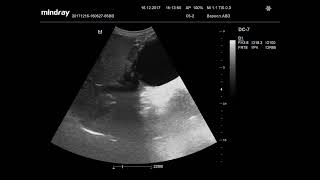

Ультразвуковая диагностика. Доктор Иогансен. Видеопримеры. Выпуск 6. Опухоли поджелудочной железы.

Представлены видеопримеры опухоли поджелудочной железы, выявленной при ультразвуковом исследовании. Ссылка на Дзен: https://dzen.ru/doktor_jogansen